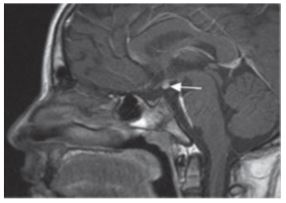

The MRI results showed an absence of the infundibulum- pituitary stalk and neurohypophysis at the intrasellar level using this study method. The adenohypophysis appeared decreased in height, without focal lesions. Imaging suggested ectopic neurohypophysis (Figure 1). These findings were consistent with PSIS.

Figure 1. Contrast-enhanced pituitary MRI (gadolinium), sagittal view: decreased adenohypophysis height without focal lesions